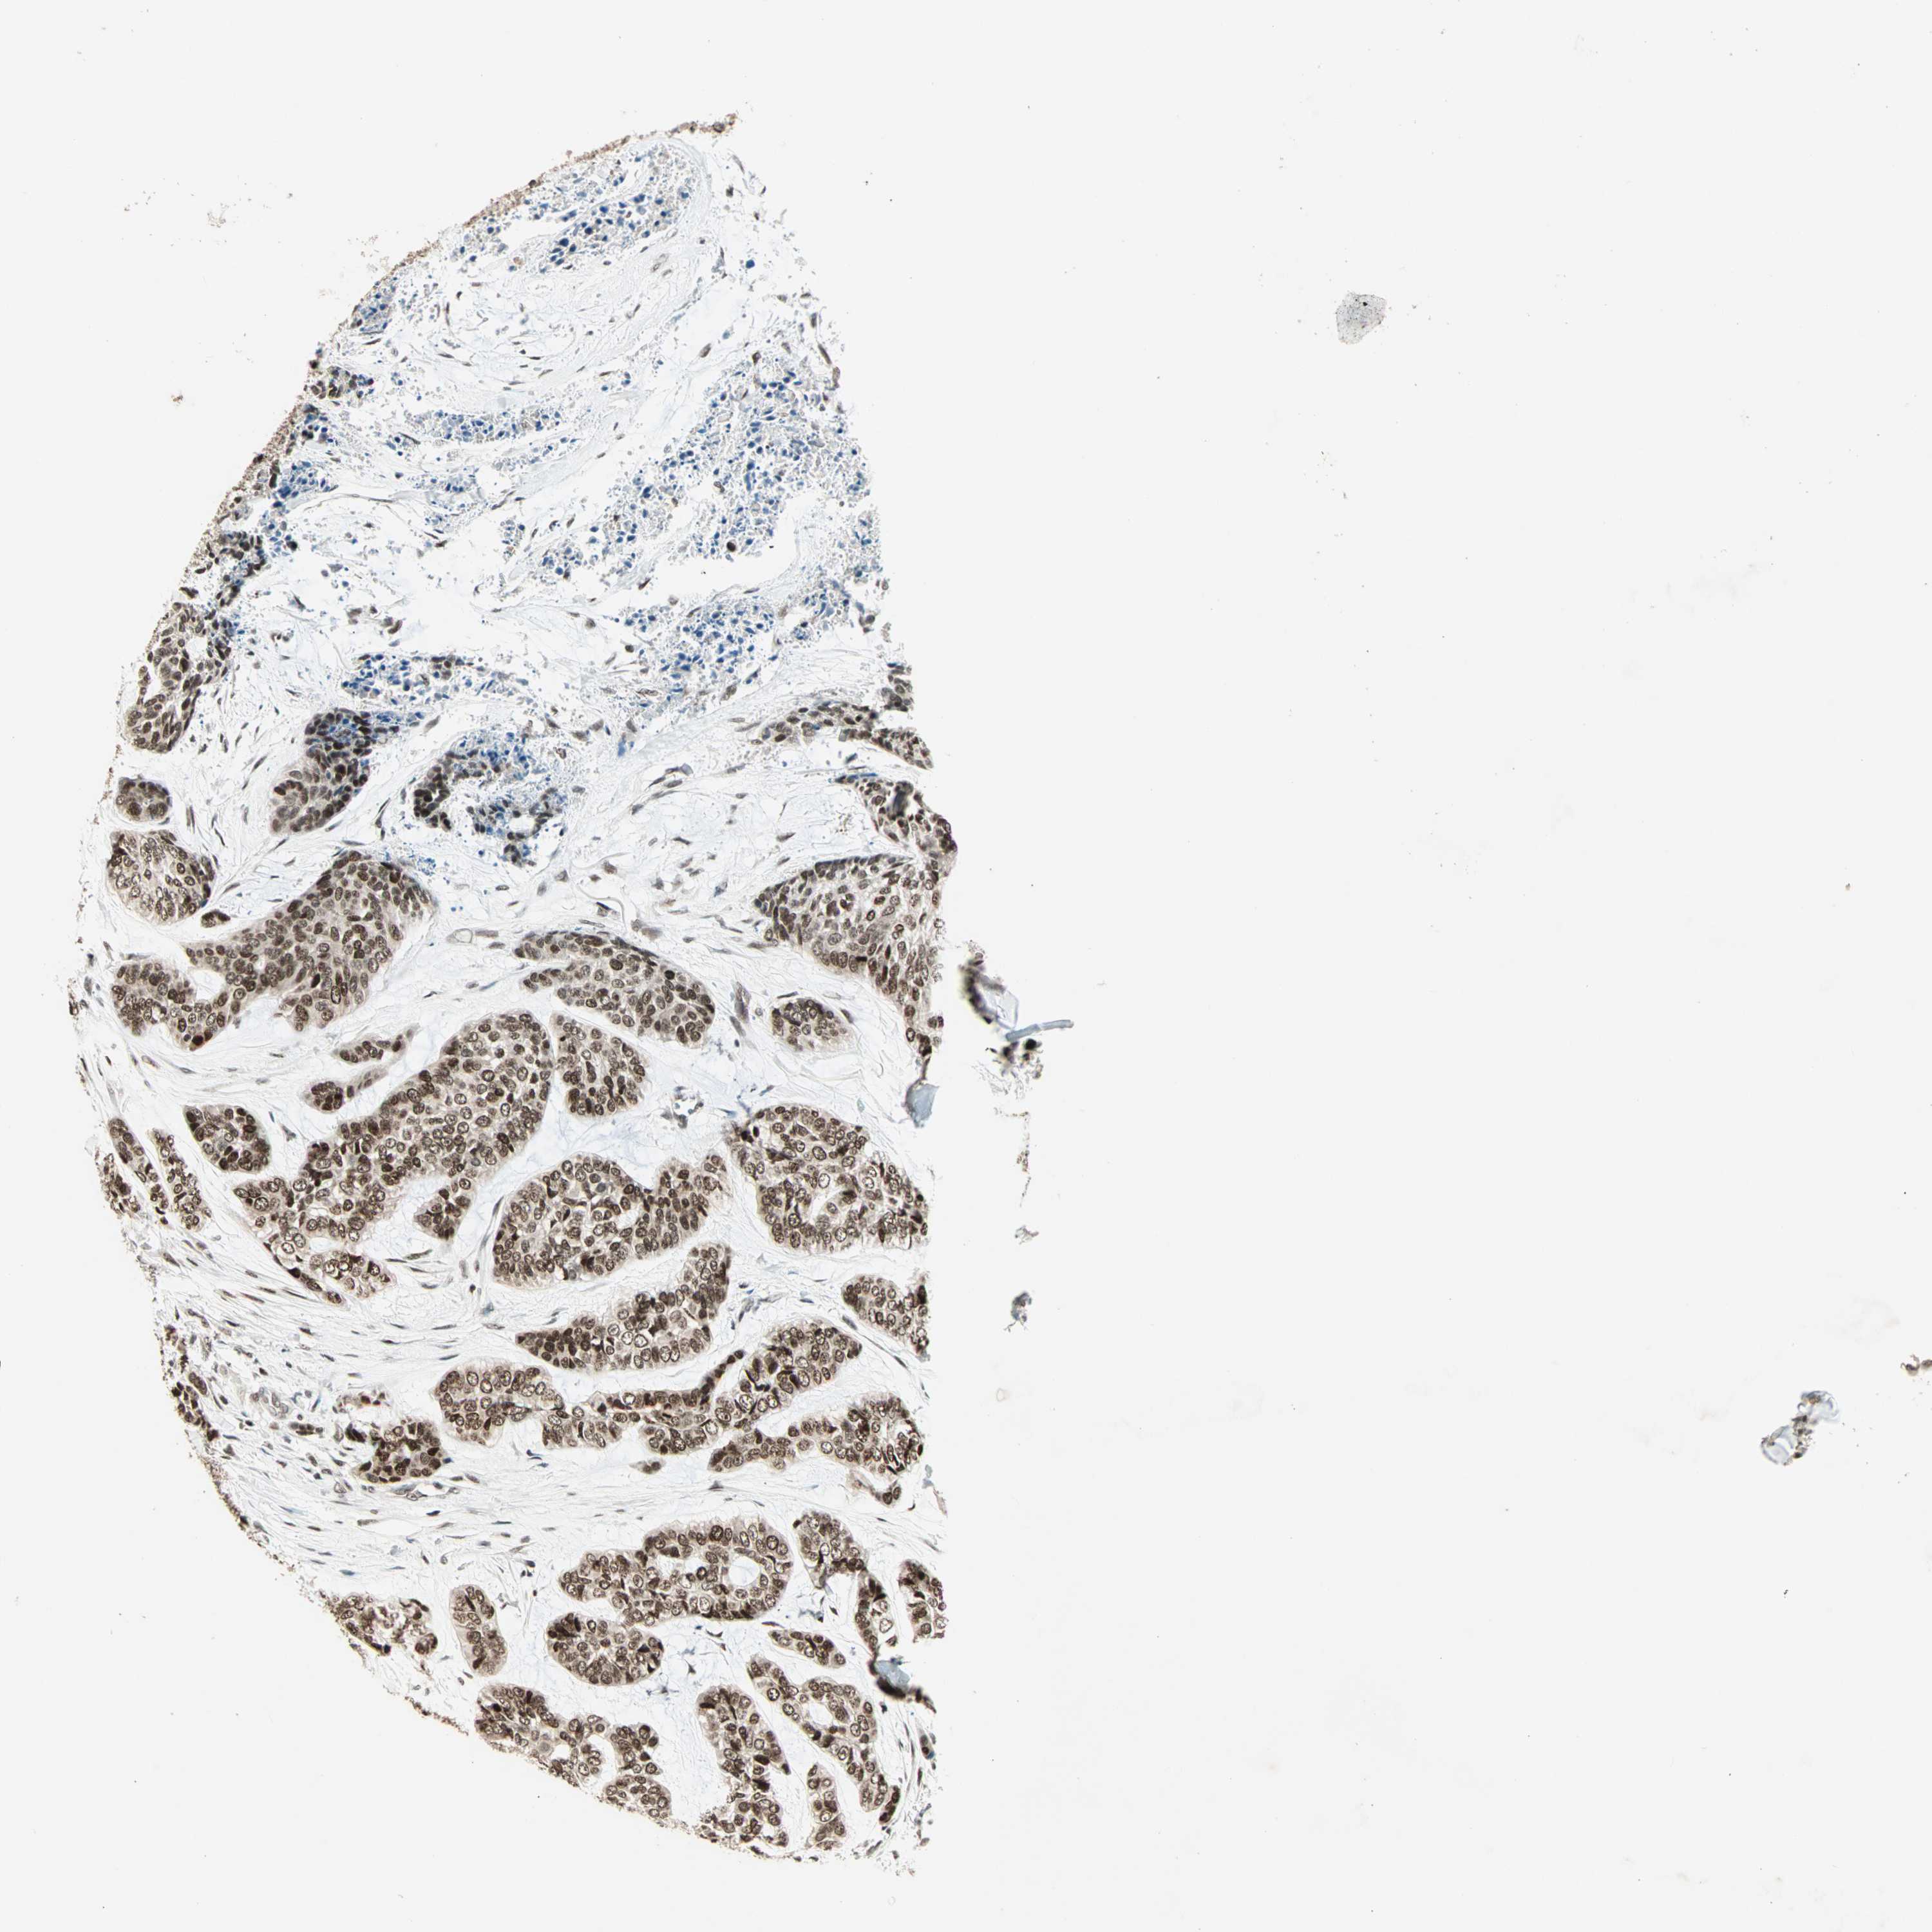

SKIN CANCER - Protein expressioni

A mouse-over function shows sample information and annotation data. Click on an image to view it in a full screen mode. Samples can be filtered based on level of antibody staining by selecting one or several of the following categories: high, medium, low and not detected. The assay and annotation is described here.

Antibody stainingi

Antibody staining in the annotated cell types in the current human tissue is reported as not detected, low, medium, or high, based on conventional immunohistochemistry profiling in selected tissues. This score is based on the combination of the staining intensity and fraction of stained cells.

Each image is clickable and will lead to virtual microscopy that enables deeper exploration of all samples and also displays staining intensity scores, fraction scores and subcellular localization as well as patient and tissue information for each sample.

Antibody HPA006915

Staining

High

Intensity

Strong

Quantity

>75%

Location

Nuclear

Squamous cell carcinoma, NOS